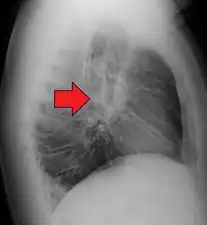

Gross pathology image showing sarcoidosis with honeycombing: Prominent honeycombing is present in the lower lobes accompanied by fibrosis and some honeycombing in the upper lungs. Honeycombing consists of cystically dilated airways separated by scar tissue resembling the honeycomb of bees. It is a nonspecific end stage of many types of interstitial lung disease.

The disease can remit spontaneously or become chronic, with exacerbations and remissions. In some cases, it can progress to pulmonary fibrosis and death. In benign cases, remission can occur in 24 to 36 months without treatment but regular follow ups are required. Some cases, however, may persist several decades.[19] Two-thirds of people with the condition achieve a remission within 10 years of the diagnosis.[145] When the heart is involved, the prognosis is generally less favourable, though corticosteroids appear effective in improving AV conduction.[146][147] The prognosis tends to be less favourable in African Americans than in white Americans.[26] In a Swedish population-based analysis, the majority of cases who did not have severe disease at diagnosis had comparable mortality to the general population.[148] The risk for premature death was markedly (2.3-fold) increased compared to the general population for a smaller group of cases with severe disease at diagnosis.[148] Serious infections, sometimes multiple during the course of disease, and heart failure might contribute to the higher risk of early death in some patients with sarcoidosis.[149][150]